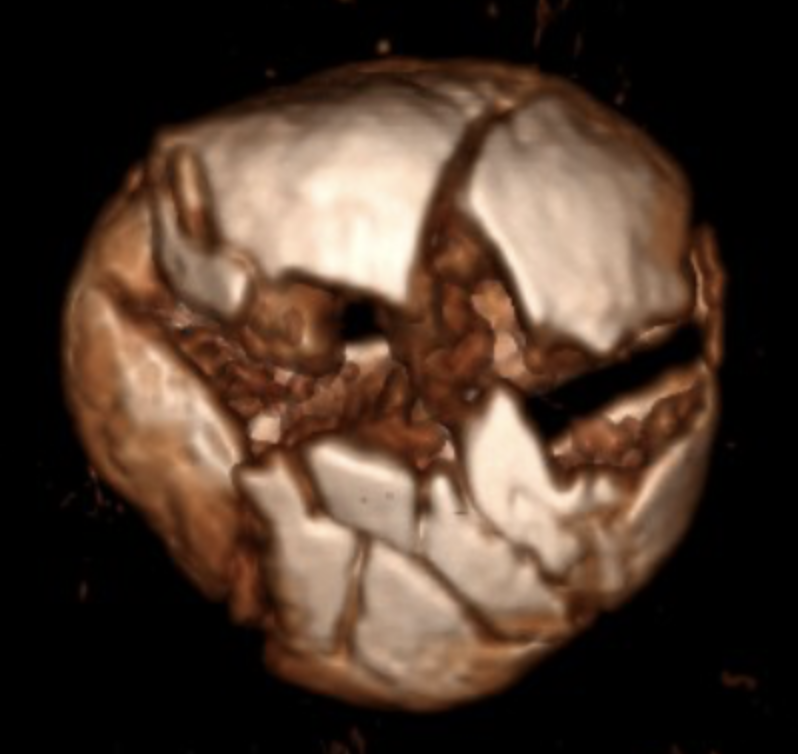

In an incredible three-hour surgery, Dr. Helfet reconstructed my shattered knee cap into no fewer than 20 pieces. Eleven months later, after a flawless recovery, Dr. Helfet and I decided to remove the 10 screws and plate. Once again, he successfully navigated surgery on my genetically fragile bone.